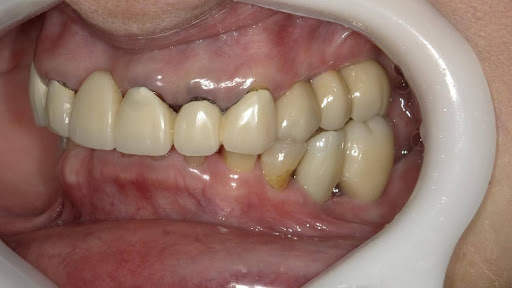

After

枚方市のインプラントの症例

T・T 様 女性 40代

症状としては、 右上5番の歯が折れてしまった。保存することは不可能な状態であった

治療法としては、患者様は、歯が折れたことを主訴に来院。インプラント治療を希望したため、抜歯した当日に、インプラント埋入をおこなって、骨欠損部には人工骨を補填した。1か月半後にインプラントが骨と結合していることを確認できたため、光学印象を行い、2か月後に、最終補綴物として、アバットメントとジルコニアクラウンの装着を行いました。

治療結果としては、抜歯したと同時にインプラントを埋入することで、抜歯した穴が自然に治る過程で、インプラントの骨結合と組織の治癒が同時に行われるために、2か月という治療期間で治療を終了することができたことと、機能面・審美面でも回復を行うができた。

治療の期間・回数:約2か月、インプラント抜歯即時埋入から最終補綴物装着まで4回

治療の価格:352,000円(税込)

治療費の内訳:インプラント基本料(フィックスチャー及び手術費用、投薬費用、レントゲン費用、インプラント上部費用(アバットメントおよびジルコニアクラウンの費用用)330000円(税込み)。オプション、抜歯即時埋入加算(人工骨費用を含む) 22000円(税込み)

治療のリスクや副作用:手術後に、痛みや腫れ、出血、合併症などを引き起こす可能性があります。噛む感覚がご自身の歯と異なる場合があります。見た目がご自身の歯と異なる場合があります。手術後にメインテナンスを継続しないと、インプラントが抜け落ちる可能性があります。